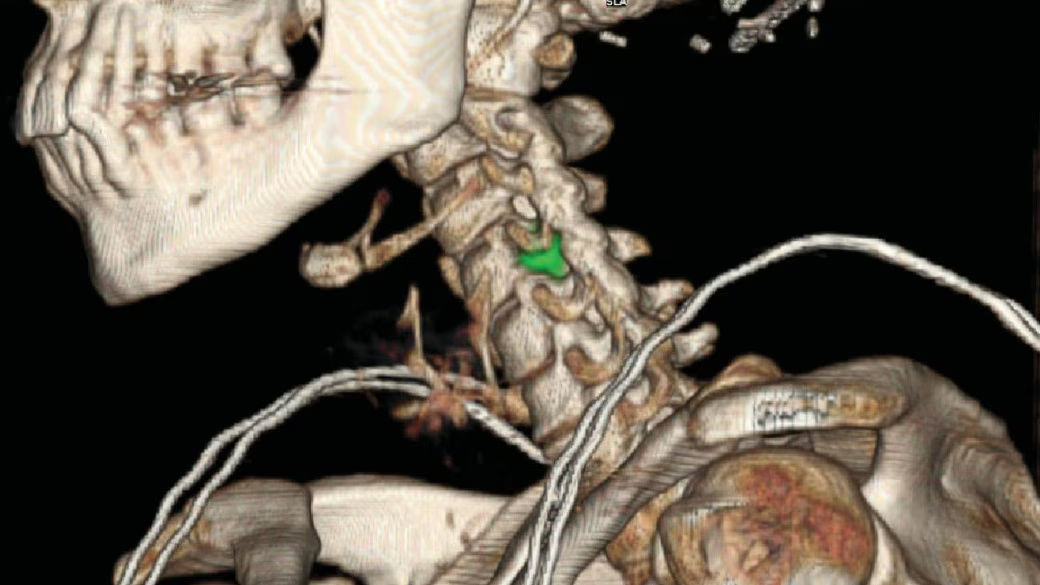

Innovative 3D design: performing in ways dual-head systems cannot

There are many reasons for a ringing endorsement of StarGuide’s constellation of 12 slim, body-orbiting CZT Digital Focus Detectors. For the technologists, each of the detectors automatically swivels into position nearest the region of interest. For clinicians, having detectors that are positioned in optimized proximity to the patient’s body contours results in increased volume sensitivity⁵ and SPECT resolution³. This proximity of this proprietary body contouring generates images with impressive detail not easily obtained on dual-head SPECT/CT systems.

Effortless and fast patient positioning to be exact

Optical Scout automatically creates a personalized topographical 3D map while positioning each patient, ensuring the optimal detector proximity and table centering in every step. Optical Scout produces a fast and safe transition from one imaging to the next. Technologists simply need to choose the protocol and begin the scanning. StarGuide’s detectors are automatically positioned in close proximity to the region of interest for each bed position to achieve the highest possible sensitivity and resolution.